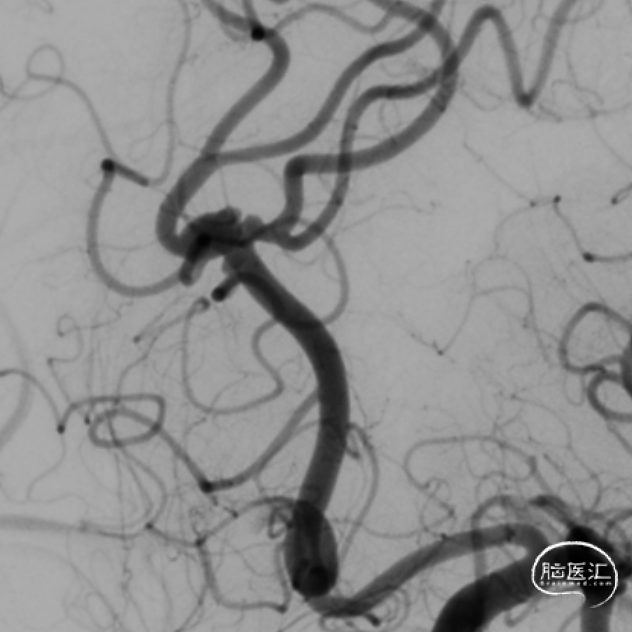

DSA:提示左侧大脑前动脉A2段动脉瘤,其他血管造影未见明显异常。

术前诊断:左侧大脑前动脉A2段动脉瘤。

治疗方案:血流导向装置植入。

微导管到位:Synchro微导丝导引支架微导管通过病变血管进入。

支架到位,远端打开(工作位):支架释放过程中,轻柔推送支架系统,支架释放,打开良好。

术后造影:支架覆盖夹层动脉瘤,贴壁良好。

术后造影:

强易达(Choydar)血流导向密网支架术中操作顺利,支架推送及释放过程平顺,未见管壁损伤,支架喇叭口形状设计贴壁效果好;径向支撑力高。